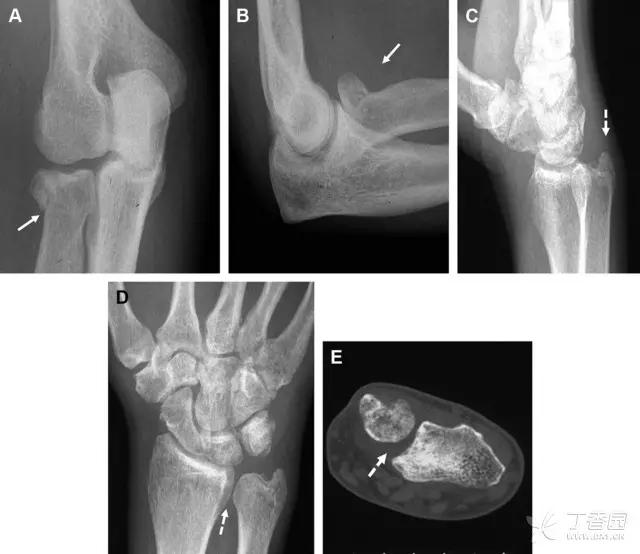

24 无移位的桡骨头/颈骨折

多发生于摔倒时,手掌撑地,受到轴向、外翻应力所致。常规的前后位片容易漏诊,常需加拍内斜位、外斜位、桡骨头-肱骨小头位片。后脂肪垫可见(位于鹰嘴窝内,一般不可见)和/或前脂肪垫抬高常提示骨性损伤。

图 2 桡骨头骨折。前后位(A)和侧位(B)片示后脂肪垫抬高(黑色箭头),前脂肪垫抬高(白色箭头),呈「帆船征」,其它表现正常;外斜位(C)和桡骨头–肱骨小头位(D)示桡骨头关节内骨折线(虚线黑箭头)累及桡骨颈(虚线白箭头)

29 Essex-Lopresti 损伤

Essex-Lopresti 损伤是桡骨头骨折伴有下尺桡关节脱位,导致骨间膜损伤,桡骨短缩。此种损伤,桡骨头骨折的诊断往往是明确的,容易忽视的是下尺桡关节脱位,特别是早期,下尺桡关节的症状不明显,X 线表示也不明显。

图 8 Essex-Lopresti 损伤。前后位(A)和侧位(B)示桡骨头关节内骨折(白色实线箭头);(C~E)伤后 1 个月复诊,患者诉腕关节疼痛,X 线(C,D)发现下尺桡关节脱位,(E)CT 进一步证实损伤的存在